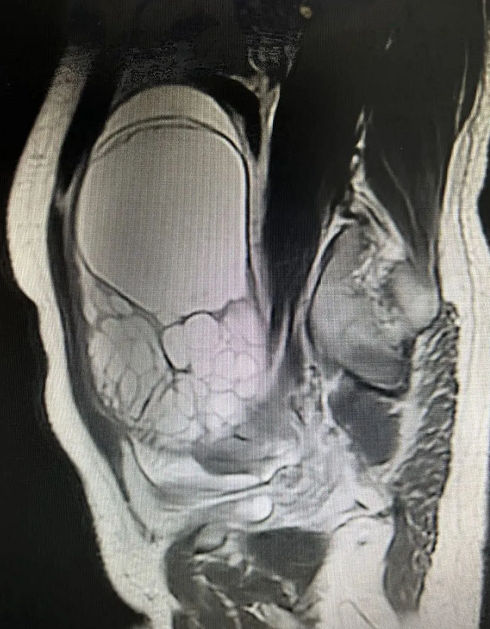

近日,海軍軍醫(yī)大學(xué)第二附屬醫(yī)院(以下簡稱“海軍醫(yī)二院”)婦產(chǎn)科主任劉曉軍教授團(tuán)隊采用上海微創(chuàng)醫(yī)療機器人(集團(tuán))股份有限公司(02252.HK,以下簡稱“微創(chuàng)機器人”)研發(fā)的圖邁?單臂單孔腔鏡手術(shù)機器人,通過臍上切口,為兩名女性患者分別成功實施卵巢巨大腫瘤切除術(shù)和全子宮切除+雙側(cè)輸卵管切除術(shù),兩項手術(shù)取得圓滿成功。